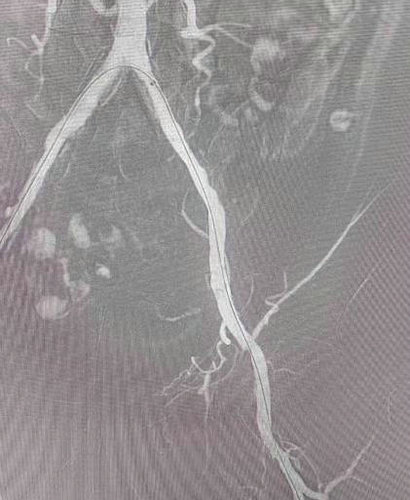

溶栓及吸栓后进行球囊后扩

术中造影显示,左侧髂动脉大量血栓栓塞伴有斑块附着,在喷药溶栓及吸栓反复三次后,应用球囊进行后扩,手术过程非常顺利,术后患者恢复明显,左下肢麻木感消失,皮温恢复正常现已康复出院。季节变换,寒气来袭,人们易发生血管收缩,而有心脏病病史的人就更需要注意房颤导致血栓脱落引起动脉阻塞,遇到这些情况需要马上到医院就诊,才能术后良好的恢复。